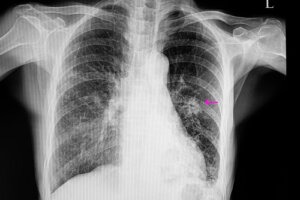

Guzek płucny to masa pojawiająca się w płucach, która może mierzyć od pięciu do trzydziestu milimetrów. Zmiana ta występuje coraz częściej i, jak się szacuje, dotyka około 0,2% populacji. Jednak prawie 60% tych guzków ma charakter łagodny.

Przyczyny tej choroby są bardzo zróżnicowane, od infekcji aż po proces nowotworowy. Większość z guzków płucnych wykrywa się przypadkowo podczas wykonywania osiowej tomografii komputerowej – lub zdjęcia rentgenowskiego.

W przypadkach zmian nowotworowych guzki zwykle mają nieregularny wygląd na radiografii, ze słabo zdefiniowanymi krawędziami. Zazwyczaj są również mniejsze niż guzki łagodne. Ponadto wiążą się wyraźnie z pewnymi czynnikami ryzyka, takimi jak:

Po wykonaniu tej czynności przystępuje się do określonych badań obrazowych w celu zlokalizowania guzka. Ponadto wyniki tych badań pozwalają na obserwację i analizę pewnych cech potrzebnych do dalszej diagnozy. Na przykład kształt i rozmiar guzka mają duże znaczenie, aby odróżnić łagodną zmianę od potencjalnie złośliwej.

Najczęściej wykonuje się rentgen klatki piersiowej i tomografie komputerową. Aby dokładnie poznać przyczynę guzka płucnego, czasami wykonuje się również biopsję w celu analizy tkanki, która go tworzy.